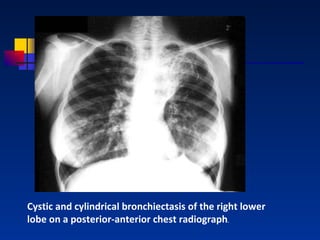

Cystic and cylindrical bronchiectasis of the right lower lobe on a posterior-anterior chest radiograph .

Cystic and cylindricalbronchiectasis of the right lower lobe on a posterior-anterior chest radiograph .